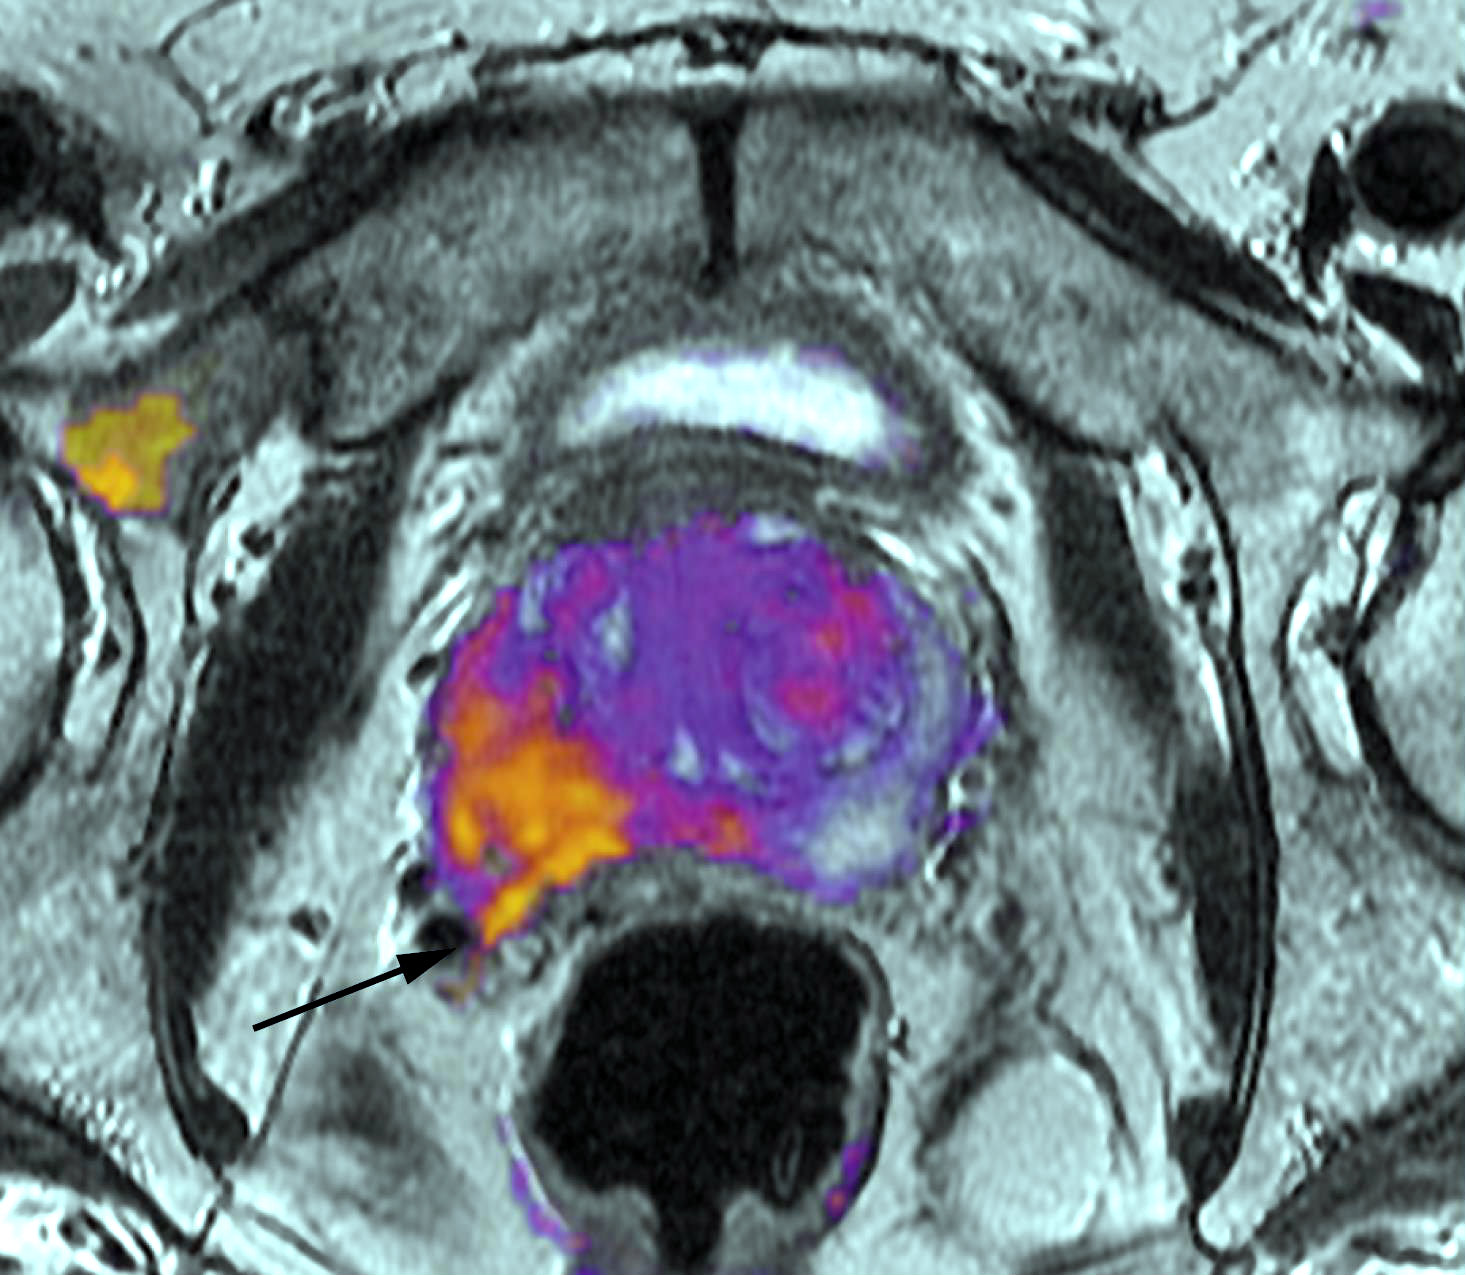

Carcinoma de próstata: novedades terapéuticas

10 abril 2018

Un ensayo clínico muestra aumento en la sobrevida del cáncer metastásico sumando quimioterapia a la terapia de deprivación androgénica. En otro estudio, la mitoxantrona no fue eficaz luego de la prostatectomía de tumores de altor riesgo sin metástasis. Journal of Clinical Oncology, abril de 2018